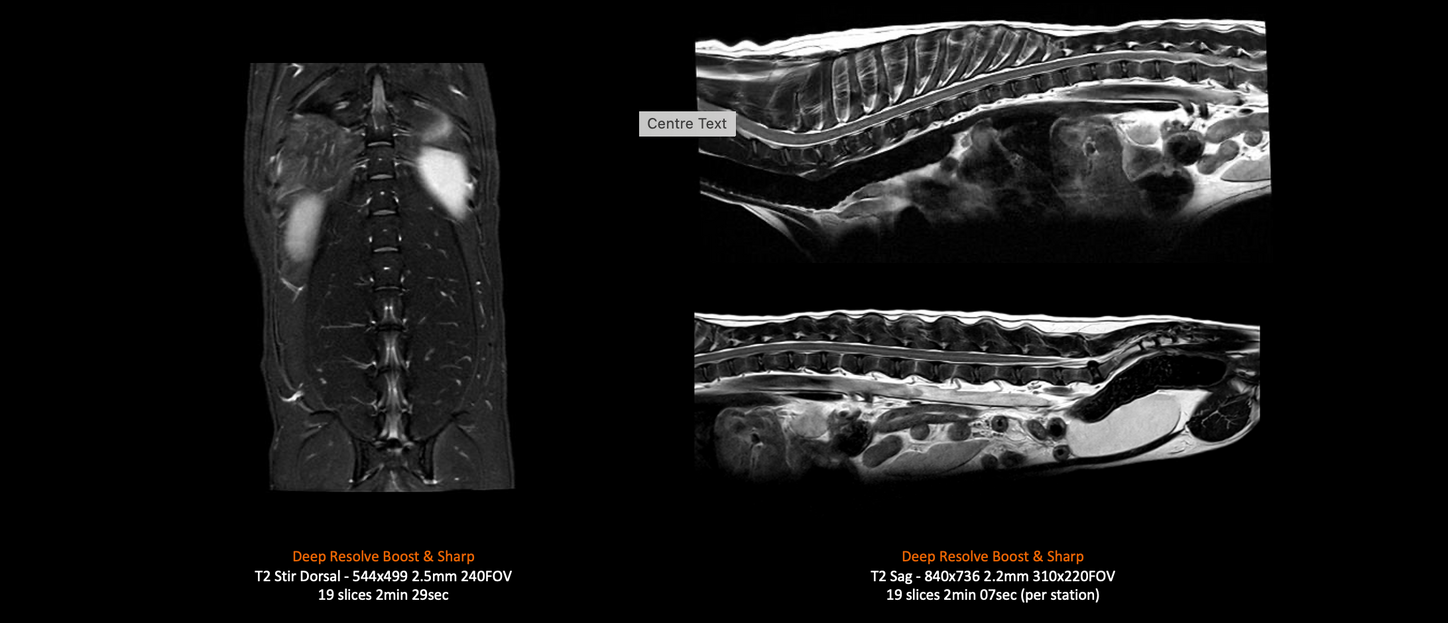

MAGNETOM Flow – 9kg Dog Spine (Spine Coil)

Deep Resolve Boost and Deep Resolve Sharp

Canine MRI Spine 14kg